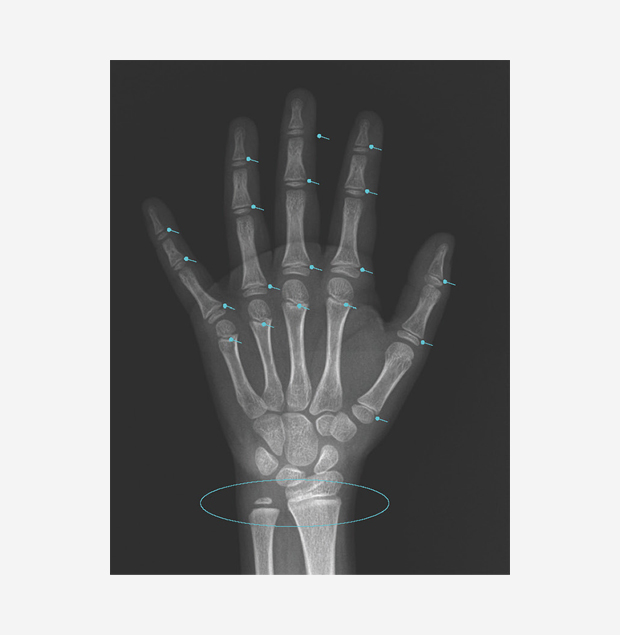

골연령 검사 (성장판 검사)

손뼈와 손목뼈 사진을 찍어 골연령을 평가하고 실제 연령(역연령)과 비교합니다.

사춘기 전 손 X-ray

성장판 닫히기 전